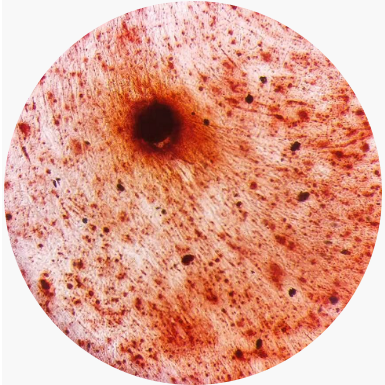

按0.6 × 104 cells/cm2接種新鮮MSC細(xì)胞至微載體培養(yǎng)液中(3g/L),4-5天后細(xì)胞可以長滿Cytodex 1,每cm2可以生長2.5 × 104 MSC,細(xì)胞在Cytodex 1上的生長照片如下圖1。

圖 1. 微載體培養(yǎng) MSC 生長圖片